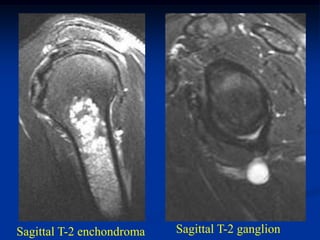

Case #554.1           Enchondroma and ganglion cyst

47 year male with shoulder pain for 6 months

ganglion

enchondroma                cyst

Coronal T-2 MRI

Sagittal T-2 enchondroma   Sagittal T-2 ganglion

Two different T-2 axial cuts showing the enchondroma

and the right cut shows the ganglion